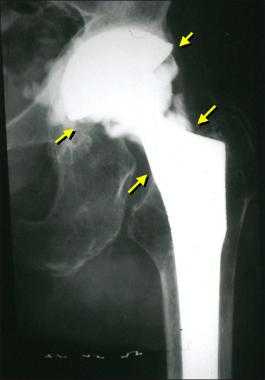

Стрелками указаны зоны инфекционного воспаления, именно так они выглядят на рентгене.